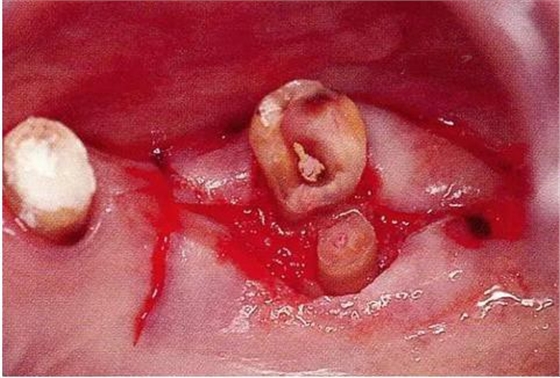

▼圖20-3

圖20-3將齦瓣剝離,完全去了除軟化牙質(zhì)的狀態(tài)。牙質(zhì)與骨緣處于相同的高度。

▼圖20-4

圖20-4為了得到生物學(xué)寬度,小心的使用車針沿著根面將骨質(zhì)切除。到達(dá)露出2mm健康牙質(zhì)的程度,已經(jīng)可以看到根面形態(tài)對(duì)于清掃已經(jīng)非常困難了。

▼圖20-5

圖20-5為了讓健全牙質(zhì)露出3mm,不得已將牙根分割。顎側(cè)牙根長(zhǎng)度不夠充分,所以判斷為無(wú)法保留。